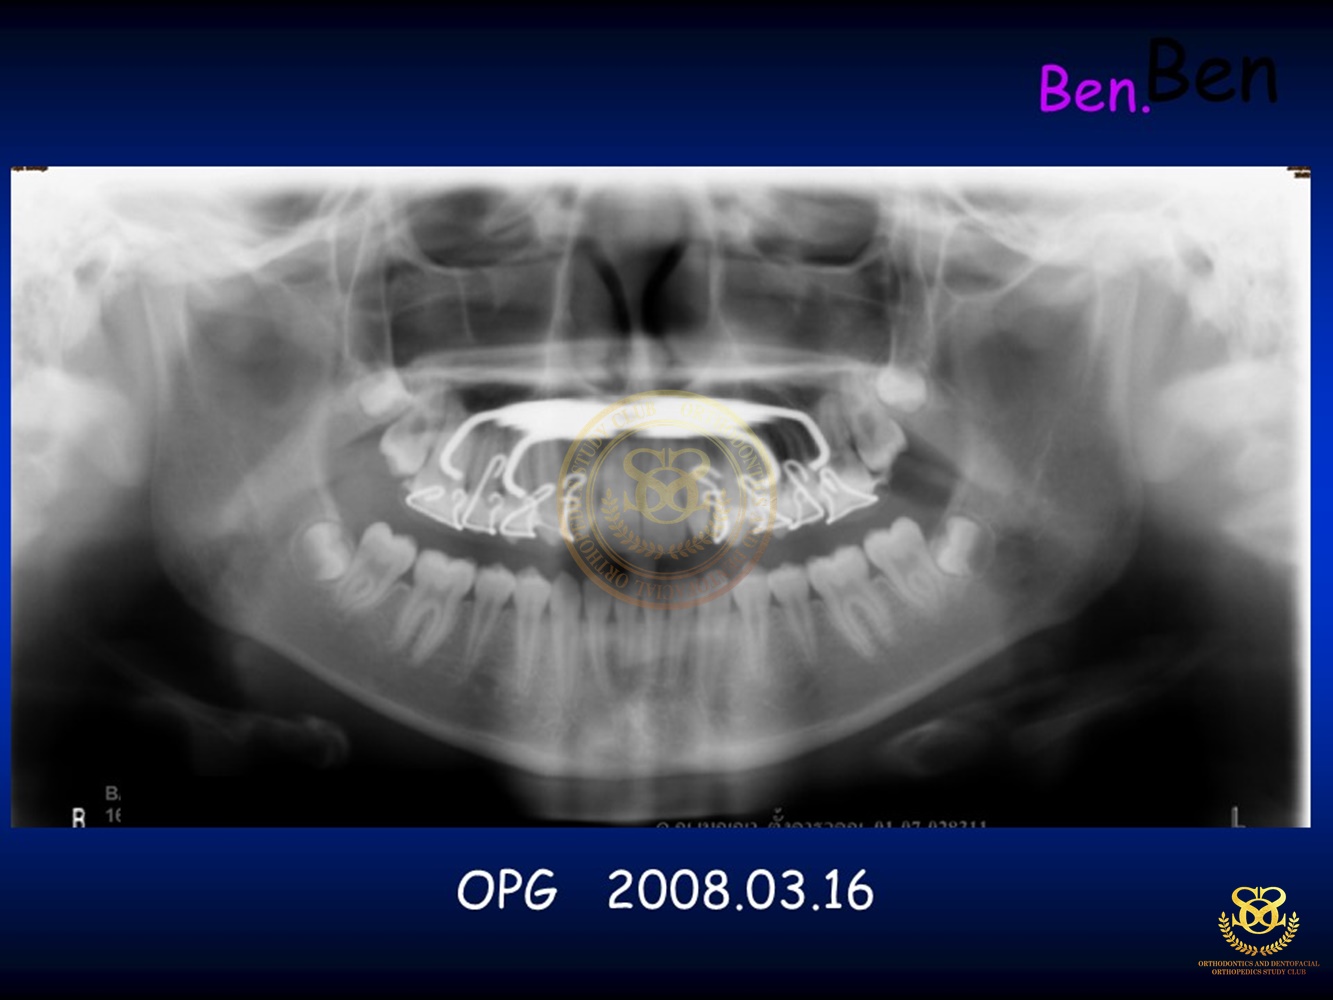

เคสตัวอย่าง Ben.Early Class III Tx.v.2018.CURRENT 2019-10-181168 views0 By Dr.Schwan Somsiri Share Share Share